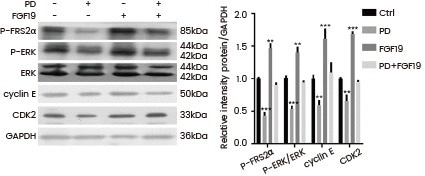

Qiao et al. utilized recombinant FGF19 (Cat#: 12226-HNAE, Sino Biological) to confirm that FGFRs mediate the FRS2α-ERK pathway in HepG2 cells. They found that FGF19 increased the levels of P-FRS2α and P-ERK, shedding light on the signaling mechanisms involved. Hu et al. demonstrated the essential role of FGF19-FGFR4 signaling in ovarian cancer cell proliferation and invasion. They used recombinant FGF19 from Sino Biological to stimulate OVCAR3 cells.

HepG2 cells were treated with FGF19 (Cat#: 12226-HNAE, Sino Biological) and/or PD and then P-FRS2α, P-ERK, cyclin E, and CDK2 protein levels were analyzed by Western blot. Image Credit: Chuchu Qiao et al.